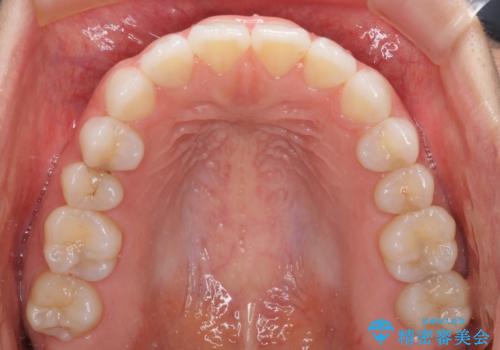

- 上下の前歯の反対咬合を気にして来院された患者様です。

インビザラインを用い、下顎はIPR(歯と歯の間を削る)と歯列全体を後方に移動させ、上顎は前歯を持ち上げることで、反対咬合を改善していくこととしました。

インビザラインによる反対咬合の改善は、上の歯が下の歯を乗り越えていく期間に咬み合わせが非常に不安定となり、治療が長期化することがあります。

こちらの患者様も、一時的に前歯でしか咬めない時期がありましたが、比較的早く咬み合わせが安定し、1年ほどで治療を終えることができました。